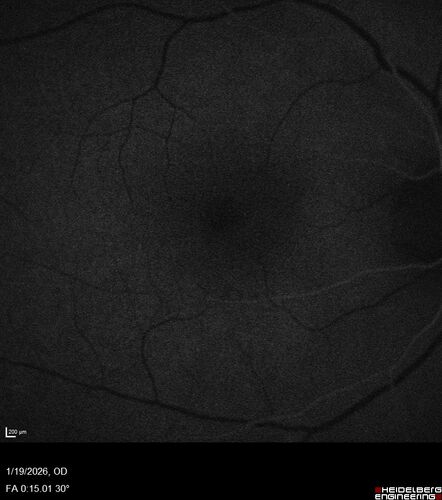

Acute Retinal Pigment Epitheliitis (Krills disease)

15 year old with sudden central vision loss in one eye. The vision loss persisted though for at least 6 months (which may be a laser injury)

Acute Retinal Pigment Epitheliitis (Maybe)